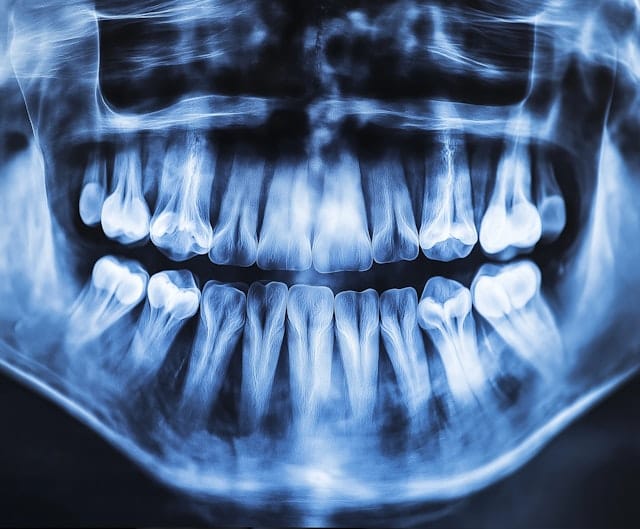

One of the key areas where AI is making a substantial difference in radiology is diagnostic accuracy. Medical imaging, such as X-rays, MRIs, and CT scans, generates complex data that radiologists traditionally analyze visually. Human interpretation, while skilled, can sometimes be subject to error or bias. AI, however, can assist by quickly analyzing these images and recognizing subtle patterns that may be missed by the human eye.

Deep learning algorithms, a subset of AI, are particularly effective at image recognition tasks. These systems are trained on large datasets of medical images and are capable of identifying specific features related to diseases such as cancer, fractures, and neurological disorders.

A great example of this is demonstrated in a 2020 study that showed AI models outperformed radiologists in detecting breast cancer from mammograms. The AI reduced false positives by 5.7% in the U.S. dataset and false negatives by 9.4%, improving diagnostic accuracy when used alongside radiologists.